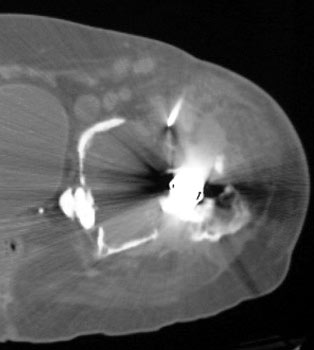

OSTEOLYSIS

Radiograph and CT

CT guided biopsy